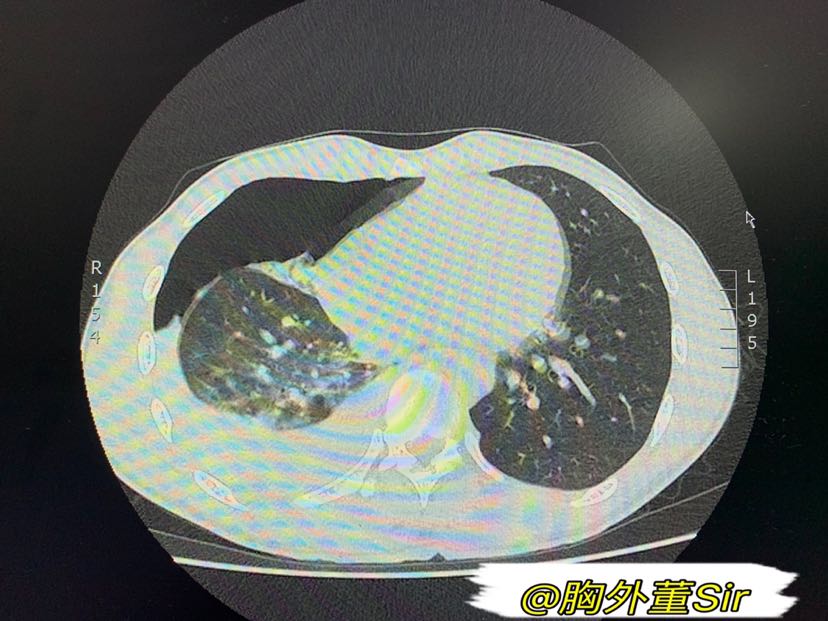

血气胸CT

ct图像显示左侧液气胸,初步估计出血量在约800ml以上